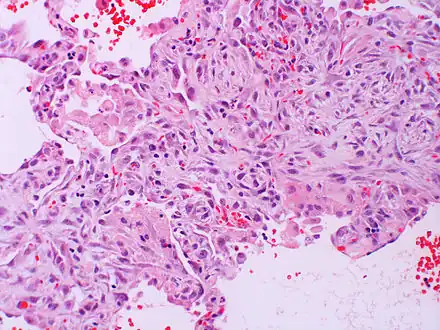

| Micrograph of diffuse alveolar damage, the histologic correlate of acute interstitial pneumonitis. H&E stain. | |

Rapid progression from initial symptoms to respiratory failure is a key feature. An X-ray that shows ARDS is necessary for diagnosis (fluid in the small air sacs (alveoli) in both lungs). In addition, a biopsy of the lung that shows organizing diffuse alveolar damage is required for diagnosis. This type of alveolar damage can be attributed to nonconcentrated and nonlocalized alveoli damage, marked alveolar septal edema with inflammatory cell infiltration, fibroblast proliferation, occasional hyaline membranes, and thickening of the alveolar walls. The septa are lined with atypical, hyperplastic type II pneumocytes, thus leading to the collapse of airspaces. Other diagnostic tests are useful in excluding other similar conditions, but history, X-ray, and biopsy are essential. These other tests may include basic blood work, blood cultures, and bronchoalveolar lavage. The clinical picture is similar to ARDS, but AIP differs from ARDS in that the cause for AIP is not known.

Acute interstitial pneumonia (AIP)/Idiopathic DAD -

Acute interstitial pneumonia (AIP)/Idiopathic DAD